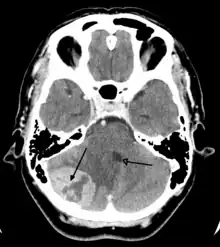

Imaging

Medical imaging plays a central role in the diagnosis of brain tumors. Early imaging methods – invasive and sometimes dangerous – such as pneumoencephalography and cerebral angiography have been abandoned in favor of non-invasive, high-resolution techniques, especially magnetic resonance imaging (MRI) and computed tomography (CT) scans, though MRI is typically the reference standard used.[37] Neoplasms will often show as differently colored masses (also referred to as processes) in CT or MRI results.

- Benign brain tumors often show up as hypodense (darker than brain tissue) mass lesions on CT scans. On MRI, they appear either hypodense or isointense (same intensity as brain tissue) on T1-weighted scans, or hyperintense (brighter than brain tissue) on T2-weighted MRI, although the appearance is variable.

- Contrast agent uptake, sometimes in characteristic patterns, can be demonstrated on either CT or MRI scans in most malignant primary and metastatic brain tumors.

- Pressure areas where the brain tissue has been compressed by a tumor also appear hyperintense on T2-weighted scans and might indicate the presence a diffuse neoplasm due to an unclear outline. Swelling around the tumor known as peritumoral edema can also show a similar result.